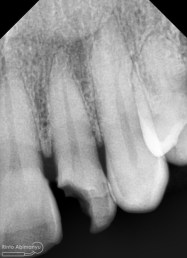

Pemeriksaan respon dingin pun menunjukkan hasil negatif, untuk menambah data dalam penegakan diagnosis maka dilakukan pengambilan ronsen pada gigi2 tersebut

Terlihat dari ronsen tersebut karies pada gigi 23 24 sudah mencapai pulpa… dari informasi pemeriksaan klinis dan ronsen maka didiagnosis gigi tersebut nekrosis.. Saya jelaskan kepada pasien mengenai kondisi gigi2 nya dan rencana perawatan yang akan saya lakukan…